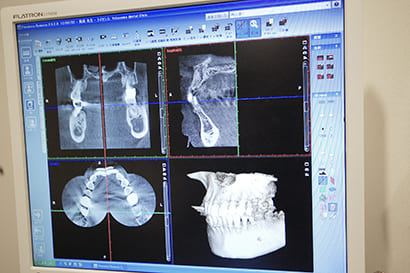

1.CTスキャンによる診査・診断

すべての歯科治療において診査診断は非常に重要です。

CTスキャンによる検査をすることで歯根の状態をしっかり把握し治療計画を立てることができます。

診査診断をしっかりすることで治療の質の向上につながります。